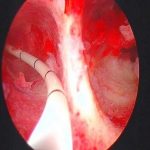

双子宫北京安太医院发明的三D腔镜下子宫融合再造手术,术后三到六个月可以备孕,可签约治疗!

新①代3D腔镜联合再造子宫3大优势

1、高清立体,360度无死角,可视化操作,精准无损

2、住院时间短,手术微创无疤痕

3、术后子宫,宫颈,阴道恢复正常形态和功能,怀孕分娩无阻碍